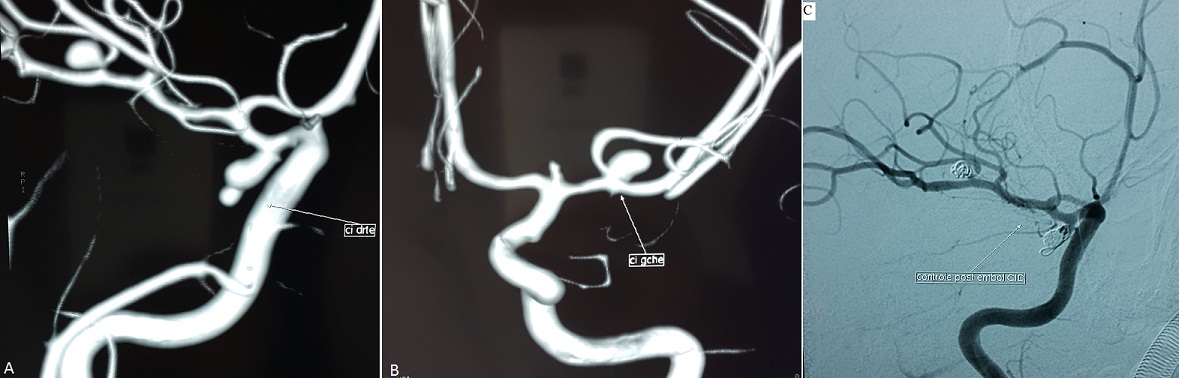

Il s’agit d’une jeune femme de 33 ans, suivie pour HTA sous monothérapie depuis un an, admise aux urgences pour des céphalées d’installation brutale. L’examen clinique trouve une patiente consciente, TA=13/7, avec présence d’un syndrome méningé franc sans fièvre. La TDM cérébrale a montré une hémorragie méningée au niveau de la vallée sylvienne droite. L’artériographie a objectivé trois dilatations anévrismales au niveau de l’artère communicante postérieure droite de 8,3mm, au niveau du segment M2 de la sylvienne droite de 4 mm (A) et enfin au niveau de la bifurcation sylvienne gauche de 4mm (B). La patiente a bénéficié d’un traitement endovasculaire des deux anévrismes à droite avec un rendez-vous de 3 mois pour sécuriser l’anévrisme gauche. La prévalence des anévrismes intracrâniens dans la population générale est évaluée de 1 à 5%. Seulement 15% de ces patients ont des anévrismes multiples, et 7% de ces patients ont plus de quatre anévrismes. La stratégie thérapeutique vise à sécuriser d’abord l’anévrisme qui a saigné et de traiter ultérieurement les autres anévrismes en fonction de leur taille et du risque hémorragique.